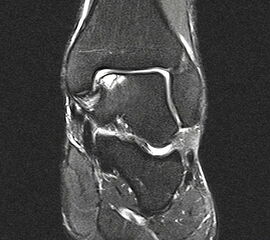

Abbildung 1: Osteochondrale Läsion der medialen Talusschulter mit subchondralem Begleitödem und Zyste.

Abbildung 1

• MRT des Sprunggelenks zur Beurteilung der Knorpelläsion, möglichen subchondralen Zysten, nekrotischen Knochenarealen und anderen Begleitpathologien (Abbildung 1).

Die Darstellung der weiteren Operationstechnik erfolgt am Beispiel eines medialen Zugangs bei einer Osteochondrosis dissceans mit subchondraler Zyte der medialen Talusschulter (siehe MRT Abbildung 1).